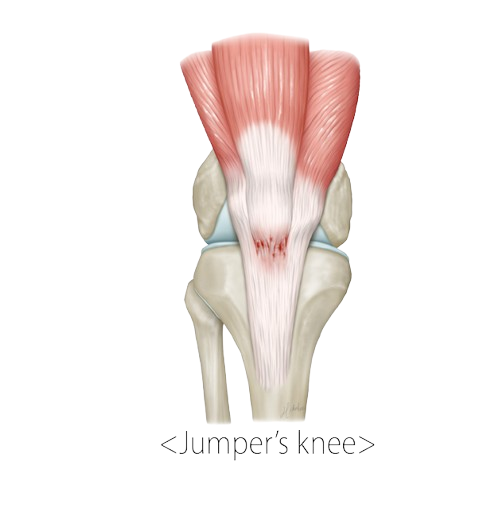

- Jumper’s knee (patellar tendinitis)